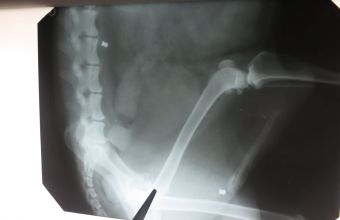

За його словами, собаку забрали у клініку, зробили рентген. На рентген світлині побачили окрім переломів ..... кулі! Дві кулі від пневматичної зброї, з якими песик жив. Це лише у задній частині тулуба, а грудну клітку і голову ж не просвічували.